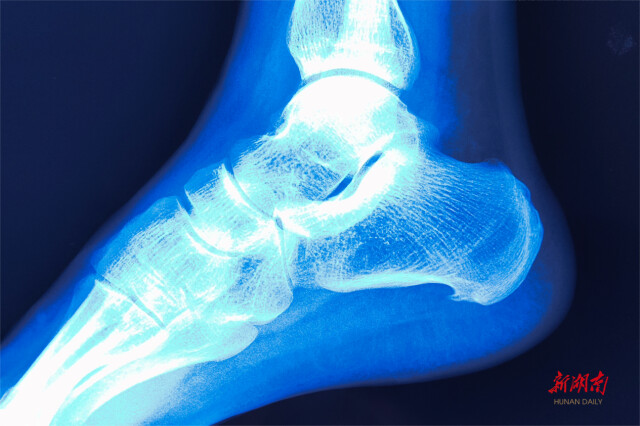

刘水平介绍,跟痛症的致病因素有过量运动、长时间站立或行走、穿着鞋履不合适、肥胖、高龄等。附着在跟骨的腱膜、肌腱反复牵拉在肌肉附着处形成骨质增生,引起脚后跟疼痛,行走或站立时疼痛更加明显,对患者日常生活造成极大影响。